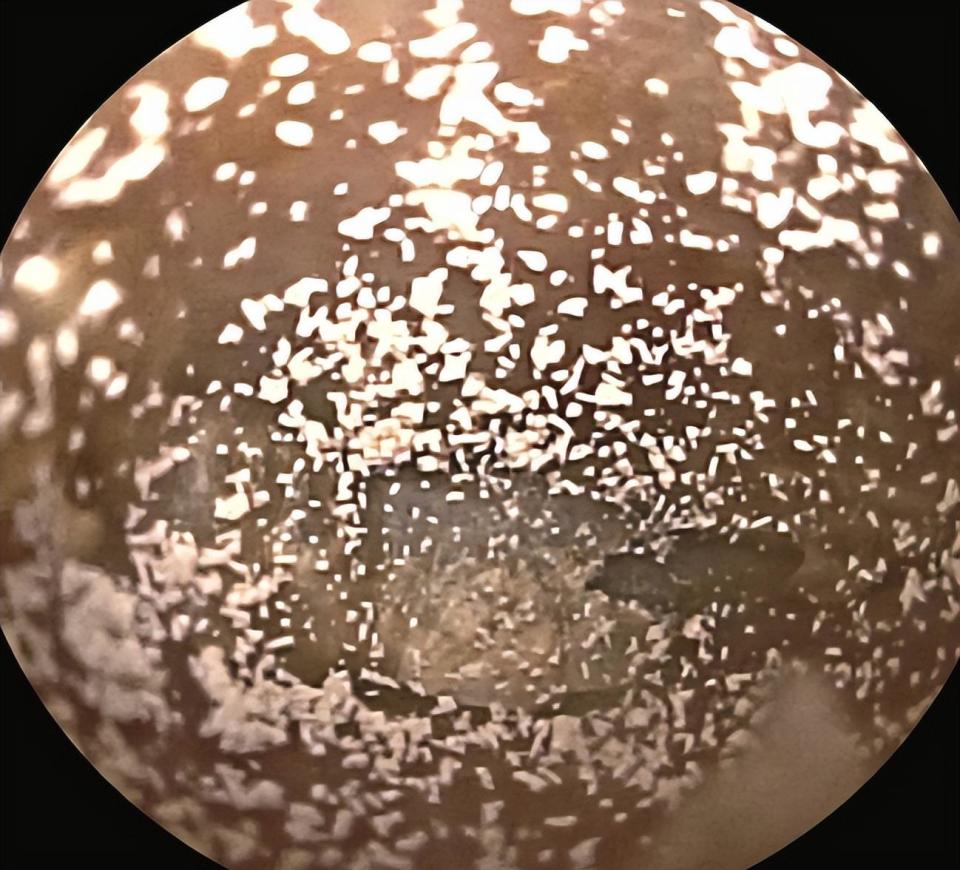

可视采耳 霉菌耳朵护理前后对比图

图片尺寸2160x2880

小姐姐耳朵非常不舒服;用采耳工具一看 整个耳道都发霉长毛了!